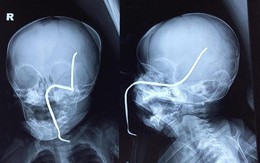

Rợn người với thanh sắt đâm thủng sọ bé gái 8 tháng tuổi

TTO - Một bé gái 8 tháng tuổi ở Sơn Tây, Hà Nội bị máy cắt cỏ vận hành gần đó làm bắn thanh sắt xuyên qua má trái gây thủng sọ.